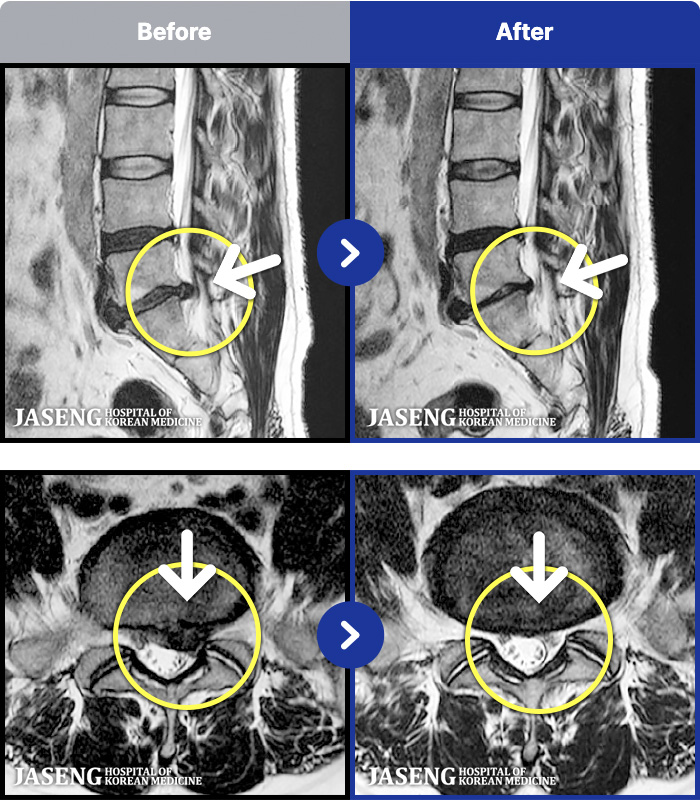

1,296 MRI ũ ʸ Ȯϼ.

ȯںп Ǹ ǿ ԿǾ, ο ġ ۿ Ƿ ġḦ Ͻñ ٶϴ.